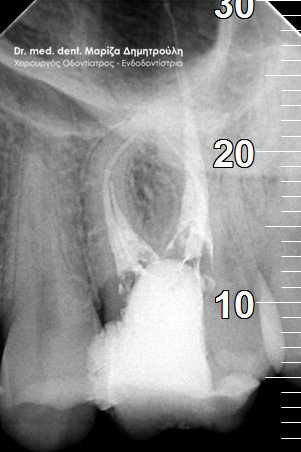

Περιστατικό – Απονεύρωση και σφράγισμα δοντιού

Ο ασθενής επισκέφτηκε το ιατρείο με σκοπό την αποκατάσταση μιας “τρύπας” που αντιλήφθηκε από μόνος του. Μετά την κλινική εξέταση διαπιστώθηκε μία τερηδονική βλάβη στον αριστερό πρώτο γομφίο. Παρόλο που η κοιλότητα δεν ήταν μεγάλη σε πλάτος η τερηδόνα εκτεινόταν έφτανε σε μεγάλο βάθος στο ύψος του πολφού, δηλαδή του νεύρου του δοντιού. Ξεκίνησε η διαδικασία της απονεύρωσης δοντιού και μετά την ολοκλήρωση της πραγματοποιήθηκε λευκό σφράγισμα σύνθετης ρητίνης. Η αποκατάσταση του δοντιού πραγματοποιήθηκε με σφράγισμα και όχι με θήκη δοντιού, γιατί το έλλειμμα του δοντιού δεν ήταν τόσο μεγάλο ώστε να απαιτείται η κατασκευή στεφάνης για την προστασία του.

ΠΡΙΝ

Απονεύρωση δοντιού

Αποκατάσταση δοντιού με προσωρινό σφράγισμα μετά το τέλος της απονεύρωσης

Τελικό λευκό σφράγισμα